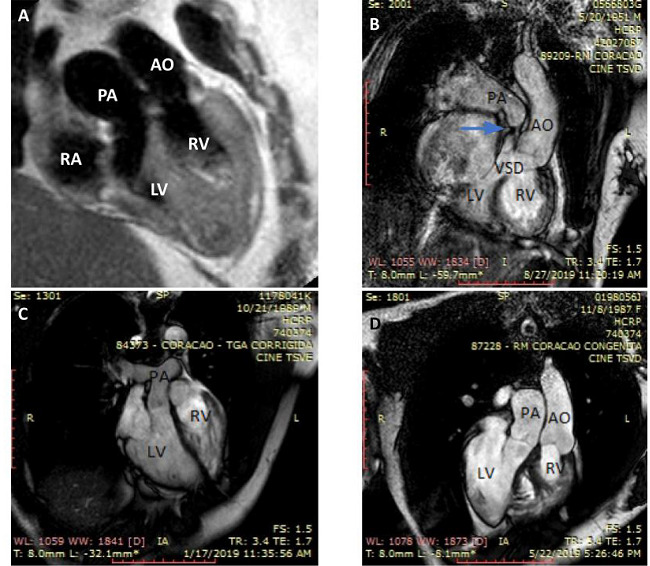

Cardiac magnetic resonance (CMR): Albeit not uniformly available, it is considered the gold standard imaging modality. Besides providing super imaging quality for vessels emerging from the heart, excellent anatomic detailing including ventricular volumes measurements and quantification of shunt and valvar regurgitation can be obtained (Figure 3). Despite of the complex morphology, cine images in short axis allow for precise RV function calculation based on systolic and diastolic dimensions[2,22]. Meticulous delineation of the RV contour outside of the trabeculations is necessary to make the method more reproducible and to determine the RV pattern of contraction. This is important since dyssynchronous RV free-wall motion in the setting of dyssynchronous ventriculo-ventricular interaction has a significant impact on cardiac output and major cardiac events have been reported even in patients who are mildly symptomatic[23,24]. Myocardial fibrosis can be detected by delayed enhancement techniques using gadolinium as contrast agent and it has been reported to be associated to progressive clinical deterioration, arrhythmia, poor exercise tolerance, and RV dysfunction[24]. Due to its high cost, CMR is not available in many centers, and, consequently, an ideal follow-up strategy might be lacking for a good number of adults who need sequential RV function evaluation for intervention planning. In paced patients, echocardiography or radionuclide ventriculography should be used.